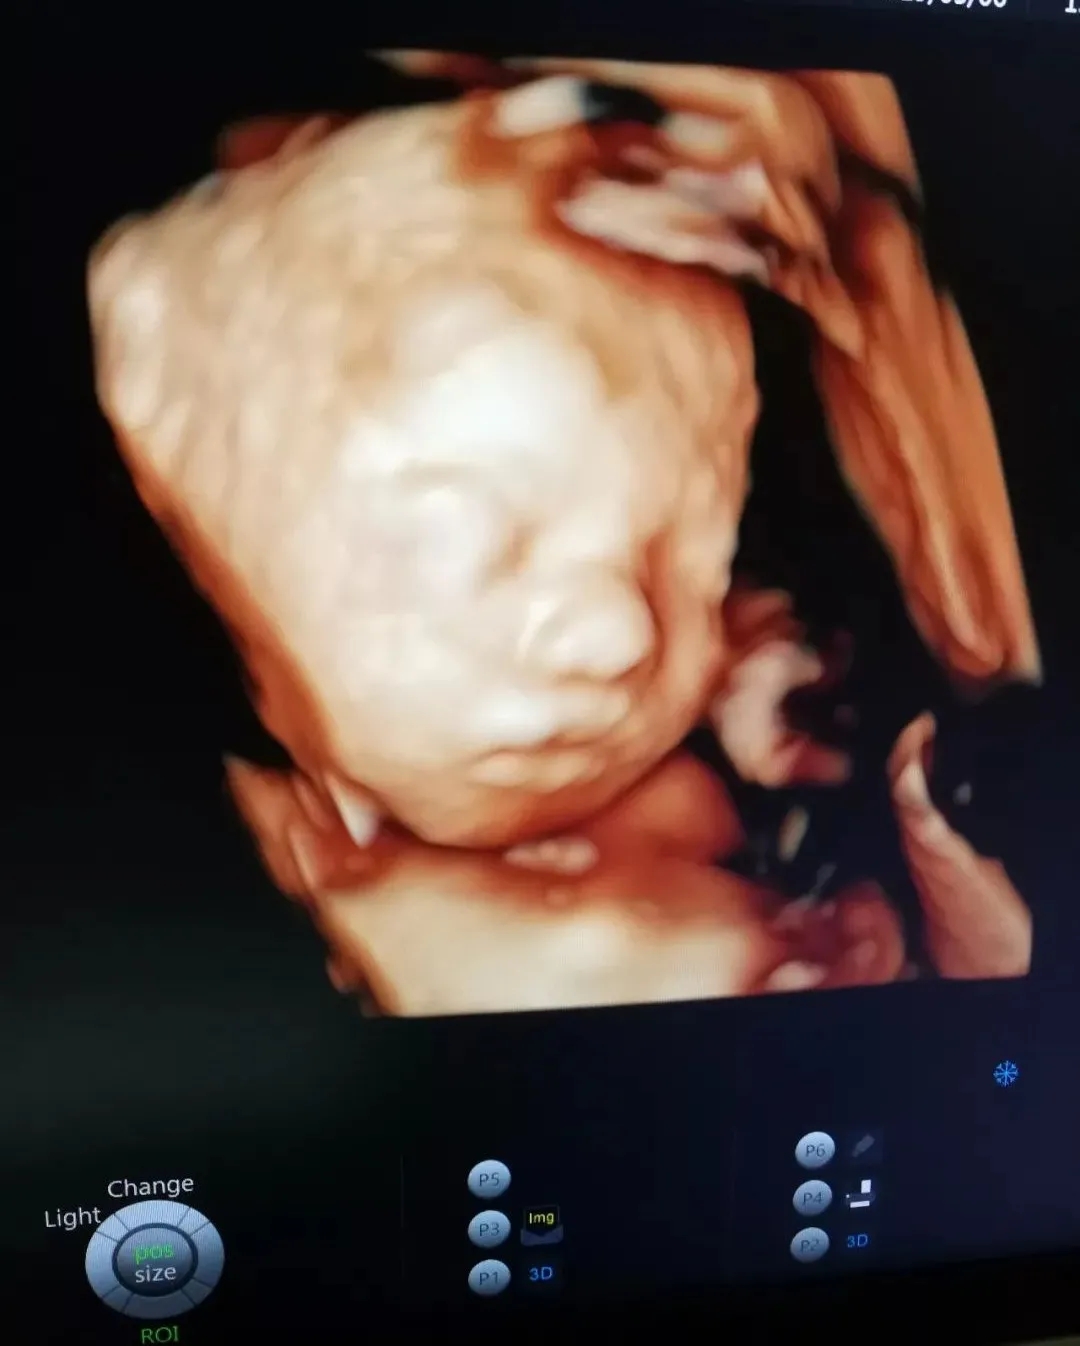

“妈妈,您昨天晚上担心我的成长发育状况,一直在做着噩梦,我很想很想跟您说,我在您腹中一直乖乖的健康成长。

我知道,妈妈您为了我健康成长,收起喜爱的化妆品与高跟鞋,告别喜爱的“垃圾”食物,每一餐都吃的精细有营养……因为我的到来,您还要承受孕吐、腰酸、水肿,承受夜里的辗转难眠。可您依旧每天满心欢喜为我准备各式各样的小衣服、小被子。

妈妈,能够做您的宝贝已经是我最大的幸福,只希望您每天都快快乐乐的!

“妈妈,您知道吗?

与您紧密相连的日子里我喜欢您轻轻抚摸肚子,听着您为我精心准备的音乐,每一天,当您睡醒的时候第一次叫我宝贝,当您遇到了开心的事情而开怀大笑,当您去练瑜伽,去看风景,当您遇到美好人和事物时,去做您喜欢做的每一件事,我都会发自内心地和您一样觉得开心。

对我来说,只要一想到您,我就情不自禁地想笑,只要一想到能做您的宝贝我就好幸福。”